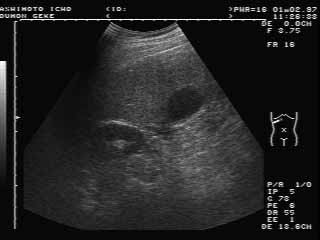

正常エコー像

ほぼ正常ですが、やや肝臓に脂肪がたまる

脂肪肝気味です。実は私のエコーでした(^^;)